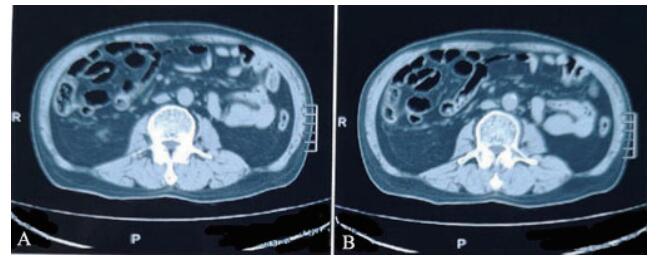

二、实验室及辅助检查血常规示白细胞14.25×109/L,中性粒细胞0.883,红细胞4.25×1012/L,血红蛋白133 g/L,血小板249×109/L。降钙素原0.44 ng/ml,CRP 59.5 mg/L,超敏CRP > 5 mg/mL。凝血检测:凝血酶原时间11.2 s,活化部分凝血酶原时间25.3 s,纤维蛋白原含量2.41 g/L,凝血酶时间11.0 s。尿常规、肝肾功能正常。抗O、RF、CCP(-)。双膝关节正侧位片无异常。腹部立位片示腹部肠管内见少量气体及肠内容物,中腹部可见小气液平面(图 1)。全腹CT示小肠肠管聚拢,肠管增宽,宽4.0 m,肝脏、胆囊、胰腺、脾脏未见异常(图 2)。

图 1 一例腹型过敏性紫癜患者腹部立位片 |